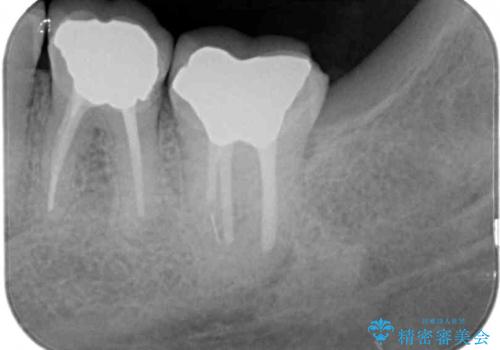

下顎の1番奥の歯であり、歯肉に覆われている部分が大きいためセラミックの十分な厚みが取れない状態でした。

十分な土台の高さを確保できない状態であったので、維持力のある土台の形態に整えることで、極力長持ちする治療を心がけました。